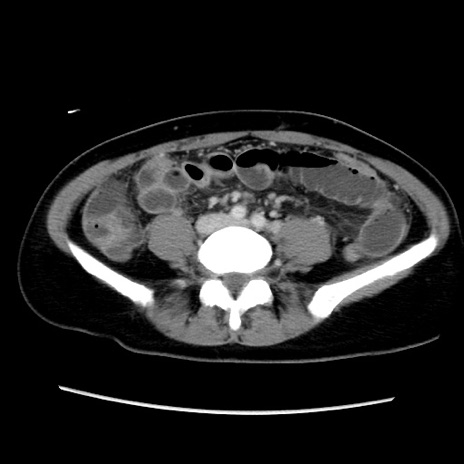

症例39(横断像)

【症例】40歳代女性

【主訴】上下腹部痛

【現病歴】2日目から下腹部痛あり。夜間は痛みで眠れなかった。昨日より上腹部痛と下痢が出現。臥位で痛みは軽快したため、休んでいた。本日になって臥位でも立位でも痛みが強くなってきたため救急要請。

【既往歴】子宮内膜症

【身体所見】部:平坦・軟、左上下腹部に圧痛あり、反跳痛あり。

【データ】WBC 21800、CRP 26.78